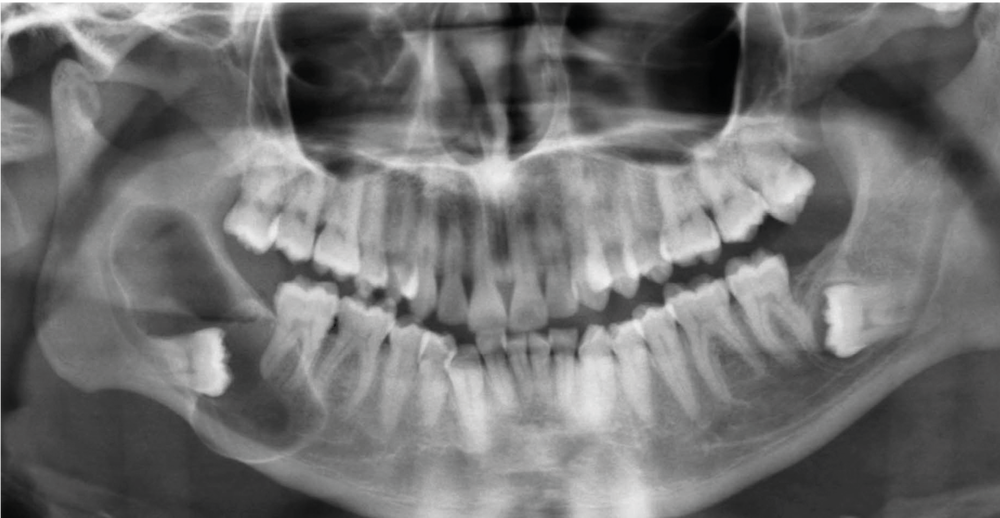

1. Panoramique initiale.

Un patient âgé de 37 ans, en bonne santé (ASA 1), se présente en consultation. Il est adressé par son chirurgien-dentiste, suite à la découverte fortuite par panoramique d’une volumineuse lésion radio-claire mandibulaire, associée à une 48 incluse (fig. 1).

La radiographie panoramique montre une large lésion radio-claire mandibulaire centrée sur la 48 incluse et s’étendant de la branche montante à la racine mésiale de 46. La lésion englobe la couronne de 48, elle est unique, homogène, ovalaire, à grand axe mésio-distal, bien délimitée par un liseré d’ostéocondensation.

Un examen complémentaire tridimensionnel par Cone Beam Computed Tomography (CBCT) révèle une lésion de 50 mm sur 20 mm, en rapport direct avec le nerf alvéolaire inférieur. Les corticales vestibulaire et linguale sont soufflées et partiellement préservées.